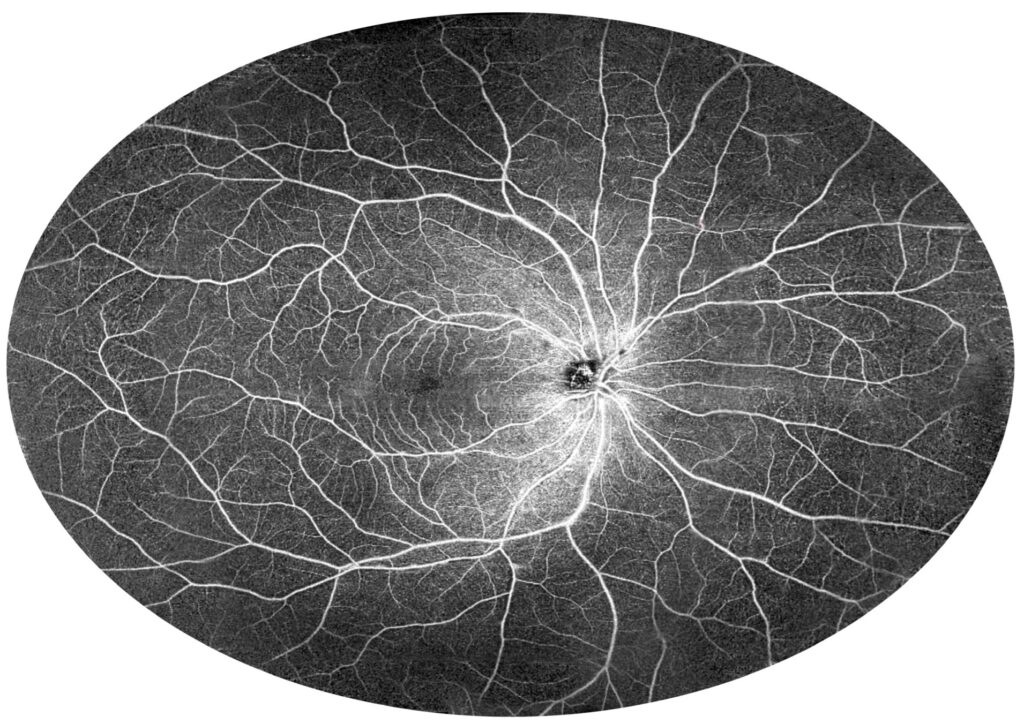

UWF imaging can be further expanded by combining UWF measurements from different adjacent locations. Figure 15 shows a mosaic of retinal UWF measurements in a healthy individual. Both macular circulation with foveal avascular zones in the centre and normal vessels at the far periphery are clearly visible. In contrast, Figure 16 shows Eales disease with peripheral ischaemia (asterisks) and collateral formation (arrows) in the temporal part of the image. Several small areas of non-perfusion can also be seen above the optic disc.

Figure 15. Healthy individual (female, age 26). The figure shows a 140-degree mosaic of 22 mm wide UWF OCT angiography measurements, showing increased imaging field of view (140-degree external field of view is equal to 210-degree internal field of view—nomenclature as in UWF Optos devices).